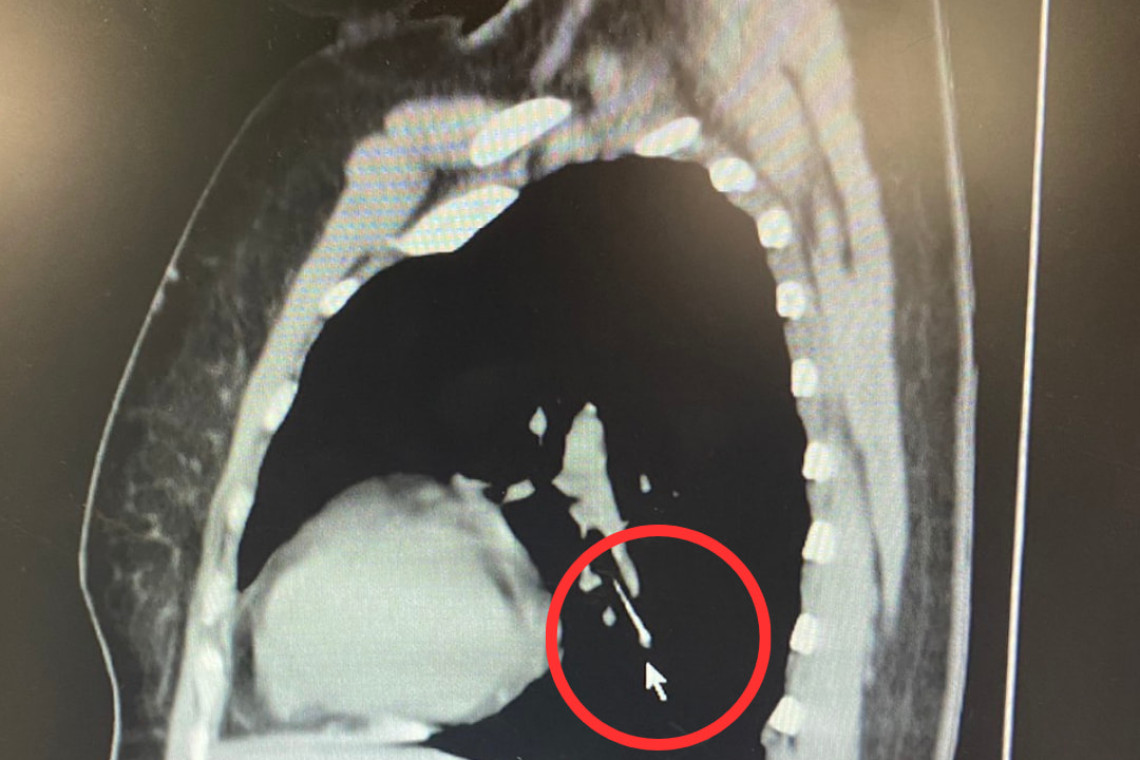

ผู้ป่วยหญิงอายุ 49 ปี ขณะเย็บผ้า ได้คาบเข็มหมุดไว้ในปาก ต่อมามีอาการสำลักเข็มหมุดหลุดลงคอ จึงได้มาตรวจที่ โรงพยาบาลนครพิงค์ ทำการตรวจเอ็กซเรย์คอมพิวเตอร์ พบว่าเข็มหมุดหลุดลงไปคาอยู่ในหลอดลมปอดข้างซ้าย

ทีมห้องส่องกล้องระบบทางเดินหายใจ นำโดย นพ.กาจบัณฑิต สุรสิทธิ์ จึงได้ทำการส่องกล้องคีบเข็มหมุดในหลอดลมออกมาได้อย่างปลอดภัย ขณะนี้ผู้ป่วยอาการปลอดภัย และแพทย์อนุญาตให้กลับบ้านได้แล้ว